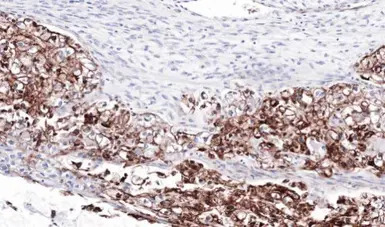

Immunohistochemical analysis of paraffin-embedded human ovarian cancer, using FLRT1(GTX105597) antibody at 1:100 dilution.

Antigen Retrieval: Trilogy™ (EDTA based, pH 8.0) buffer, 15min